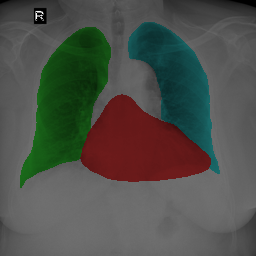

To bridge the methodological gaps when only small-scale partially labeled data is available, we propose a simple yet efficient framework Vicinal Labels Under Uncertainty (VLUU) by exploring the statistical similarity of human structures (e.g. shape, size, location) among different patients. See Fig. 1 for an illustration of such a similarity. The proposed framework is motivated by vicinal risk minimization (VRM) [11], where the fully labeled vicinal examples are generated by linearly combining randomly sampled partial labels with a weight randomly sampled from a Dirichlet distribution. These vicinal examples allow us to transform the partially supervised problem into a fully supervised one. That is to say, we can utilize any existing supervised segmentation networks and loss functions to solve partially supervised problems. The generated vicinal labels contain uncertainty regions where classes of interest could potentially overlap. We utilize these uncertainties in the training process to improve the robustness of DL models.

In standard adversarial training, the segmentation network and the discriminator play a zero-sum game. The discriminator is trained to discriminate the prediction masks produced by the segmentation network from the ground truth masks. Meanwhile, the segmentation network is trained to confuse the discriminator by producing realistic prediction masks. Adversarial training benefits from the human structure similarity as it makes the unknown true label distributions easier to be caught by the discriminator than for general objects [38]. In other words, there is smaller instance-wise variation in the size, shape, and location of human organs (or structures), as shown in Fig. 1, than for general objects.